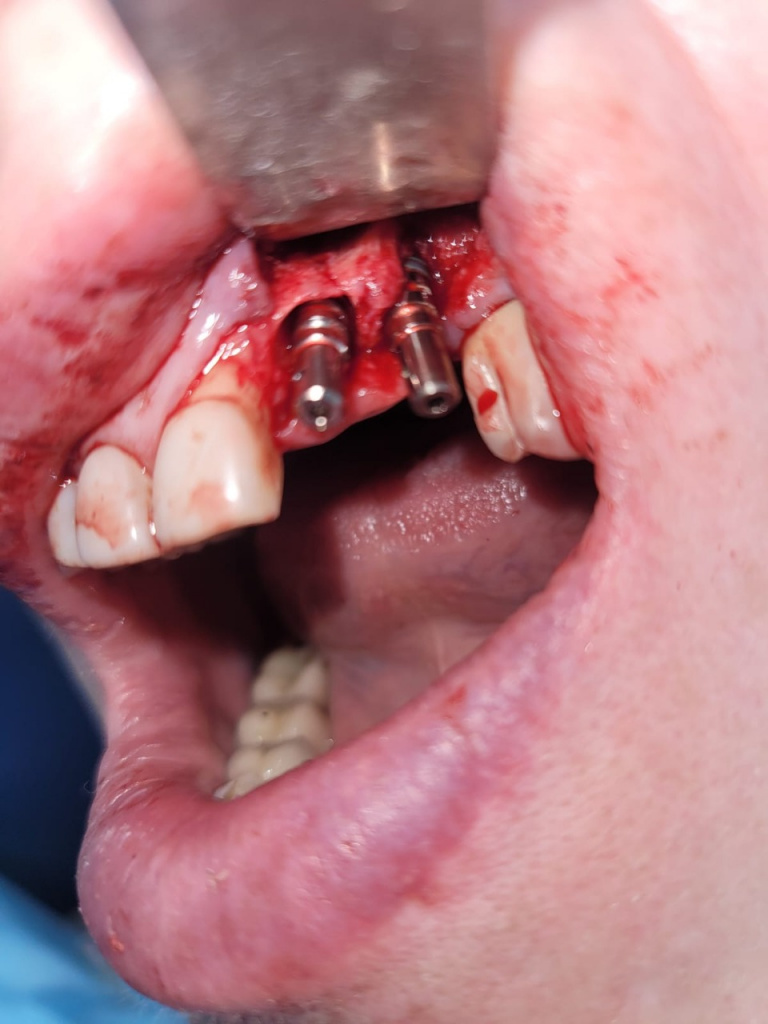

План: удаление имплантата 22 с одномоментной установкой имплантатов 22, 23 (зуб 23 уже удален к моменту операции). Плюс немедленная нагрузка временными коронками.

Установлены имплантаты с укороченным протоколом сверления (2.0 на всю глубину, фреза 3.3 на 7 мм):

Импро Респект 4.5х12, торк более 40 Н/см.